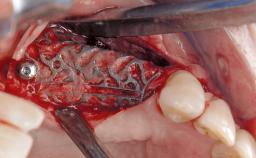

Late Presentation of Peri-Implant Mucositis Requiring Soft-Tissue Augmentation and Esthetic Crown Lengthening at Implant Site 11

Biological or technical complications around implant-supported prostheses place a significant burden on patients as well as the surgical and restorative team. Inflammation of the peri-implant soft tissues is often the first sign that something has gone awry. While there is never a good time for a complication, late presentation of inflammation in the soft tissues around a long-standing prosthesis triggers a period of research and review of the case in order to ascertain the treatment history and its possible contribution to the etiology of the situation. This becomes more complicated in situations where a patient has not received regular maintenance and clinical/radiographical examinations due to personal, financial, or professional reasons. When the complication occurs in the esthetic zone, the complexity of the situation expands exponentially, as the only acceptable outcome in the patient’s eyes will be the maintenance of the esthetics of the prosthesis.

Bone Augmentation -

Augmentation Materials -